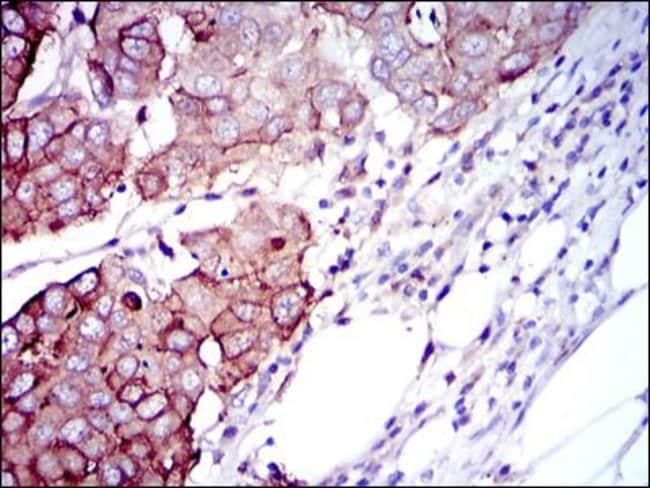

MA5-17168 targets RPS6KB1 in FACS, IHC, indirect ELISA, and WB applications and shows reactivity with Human samples. The MA5-17168 immunogen is purified recombinant fragment of human RPS6KB1 expressed in E. Coli. MA5-17168 detects RPS6KB1 which has a predicted molecular weight of approximately 59kDa.

RPS6KB1 (p70S6K) is a serine/threonine kinase with 2 non-identical kinase catalytic domains which phosphorylates several residues of the S6 ribosomal protein. p70 S6 kinase is predominantly localized in the cytoplasm, and is essential in growth factors regulated cell proliferation, pathways involving cell motility, such as metastases, the immune response, and tissue repair. p70 S6 kinase acts downstream of phosphoinositide (PI) 3-kinase, and its main physiological target is the S6 ribosomal protein, which is involved in upregulation of protein synthesis. The kinase activity of p70 S6 kinase leads to an increase in protein synthesis and cell proliferation. Amplification of the region of DNA encoding p70 S6 kinase and overexpression are seen in some breast cancer cell lines.

ELISA, Flow Cytometry, Immunohistochemistry (Paraffin), Western Blot